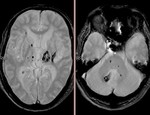

[画像診断]脳内の多発海綿状血管腫について<続き> 2010-08-12

[画像診断]脳内の多発海綿状血管腫について 2010-08-11